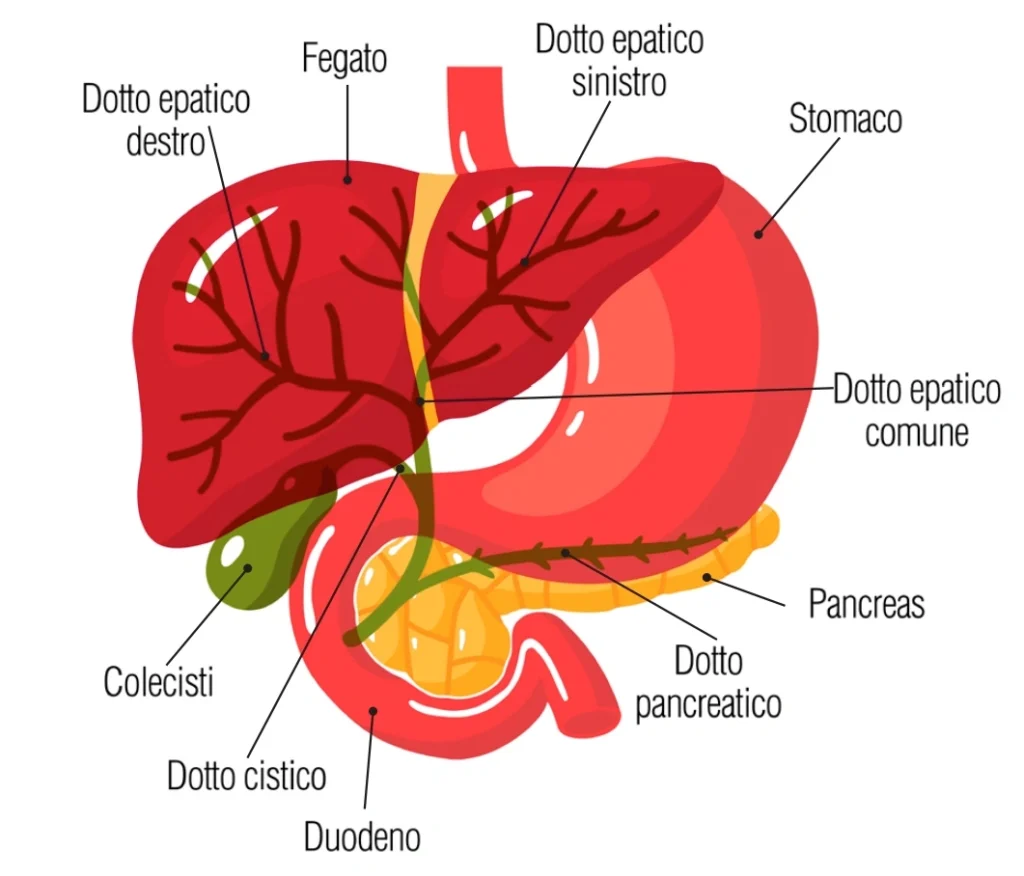

Cosa Sono le Vie Biliari?

Le vie biliari sono una rete di canali e organi che giocano un ruolo essenziale nel processo digestivo. Comprendono la colecisti e i dotti biliari, che sono responsabili del trasporto della bile, un fluido prodotto dal fegato che aiuta nella digestione dei grassi.

La colecisti è un piccolo organo a forma di sacco situato sotto il fegato, nell’addome superiore. La sua funzione principale è immagazzinare la bile prodotta dal fegato fino a quando non è necessaria per la digestione. Durante i pasti, la colecisti rilascia la bile nell’intestino tenue per facilitare la digestione.

I dotti biliari sono una rete di canali che trasportano la bile dal fegato e dalla colecisti fino al duodeno, la prima parte dell’intestino tenue. I dotti biliari comprendono:

- Dotti epatici destro e sinistro, che si originano nel fegato e si uniscono per formare il dotto epatico comune.

- Il dotto cistico, che proviene dalla colecisti, si unisce al dotto epatico comune formando il dotto biliare comune.

- Questo dotto biliare comune passa dietro il pancreas e si unisce al dotto pancreatico all’ampolla di Vater, prima di aprirsi nel duodeno, dove la bile è rilasciata per facilitare la digestione dei grassi.